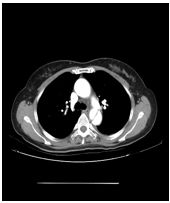

3. 病人18歲女計程車無線呼叫員, 到院主訴有五天的間 歇性燒熱及寒顫(chillness), 並合併頭痛、雙眼後疼痛及全身肌疼, 經初步診斷腦膜炎, 病人拒絕腰椎穿刺檢查, 乃試用抗生素後回家療養。 唯症狀仍舊, 尚有噁心、嘔吐, 並先後在左大拇指及右小趾出現疼痛紅斑(如圖A及B所示)。既往病史有二尖瓣膜脫垂及閉鎖不全。理學所見身高:162cm;體重:45Kg;BP:105/67mmgHg;T/P/R: 39.8C/155/18。未見Meningeal signs. 頸部末見異常, 心尖在left 5th ICS, mid-clavicular line, 有Grade III/VI Pansystolic murmur. S1及S2正常。胸、腹都無不正常。實驗室檢查: WBC:4.39x k/uL,有left shifting;RBC:5.12 x M/uL;Hb:11.0 g/dL;Platelets:130 x K/uL;其血液細菌培養結果如與胸部X光詳見附圖C、D。心電圖如附。本病人經過下列臨床處置